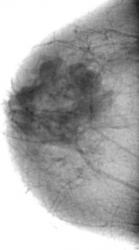

Случай 1.     Опухоль молочной железы - "рак" в виде "узлового образования". Случай Рыбаковой Л.А.

В окружающей, "узловое образование" ткани определяется перестройка - трансформация структуры (архитектоники) по "хаотическому типу". Контуры узлового образования, в основном неровные, с тенденцией полицикличности, нечеткие. По верхнему контуру преобладают "линейные" - спикулоподобные структуры, напоминающие формирование "корона малигна".

Структура "узлового образования" неоднородная, с отдельными различной формы уплотнениями.

При детальном анализе "тени опухолевидного образования" создается впечатление, что тень является конгломератом, состоящим из отдельных округлых образований, что свидетельствует о том, что опухолевый рост "происходил" из нескольких "точек роста".

На фоне отдельных узлов дифференцируются глыбчатые и точечные "уплотнения".